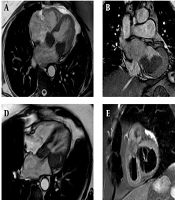

Case Report

Cardiac Inflammatory Pseudotumor Following Atrial Septal Defect Repair: A Rare Complication Managed with Sirolimus and Bevacizumab

Mersad MehrnahadORCID,

Hamidreza PouraliakbarORCID,

Ali MohammadzadehORCID,

Mansoor NamaziORCID*

|

Final Published